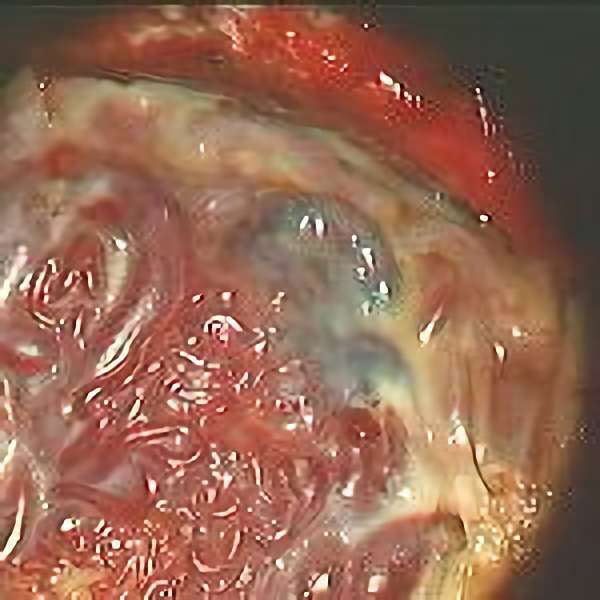

No.359 手術中

No.359 手術後

出血既往があり。2回の手術前血管内手術の後に、

Lateral transpeduncular approachにより再々出血予防を目的に

摘出手術を行う。完全摘出であることを確認した。

手術による合併症や後遺症なしで退院した。経過良好。